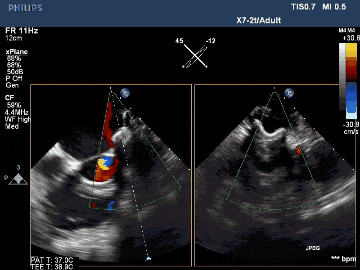

術(shù)后TEE影像示封堵完全